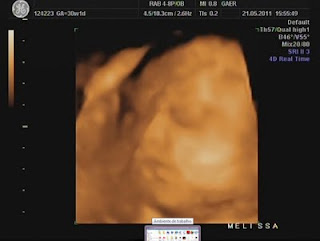

Hoje foi dia de análises e eco...

Durante a eco, percebi que a Dra ficou tempo a mais a avaliar o mesmo local e ao fim ela me explicou que viu uma lamina de água a volta do coraçãozinho da minha pricesa.

Ela me explicou que isso acontece a alguns bebés e que não devo me preocupar, que temos que fazer um exame mais detalhado para avaliar o coraçãozinho dela que será feito no Hospital São João e que hoje já trataria de marcar isso...